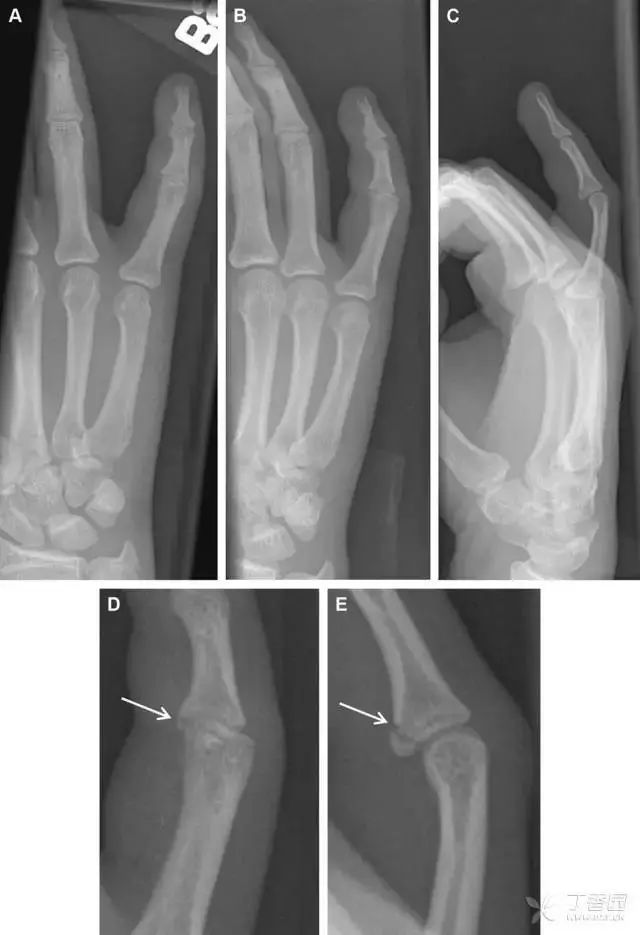

掌板骨折

掌板是掌指关节和指间关节关节囊掌侧的纤维结构,防止关节过伸。掌板的远端部是增厚的纤维软骨,附着于指骨掌侧基底部,而其两侧与侧副韧带的纤维融合。掌板骨折多发生于过伸损伤,为撕脱性骨折。

图 3 掌板骨折(A~C)小指前后位、斜位、侧位片,由于骨折的部位及特点,在前后位片上通常难以发现骨折;放大后的斜位(D)、侧位(E)可见一骨碎片(白色箭头)。